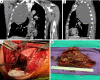

Figure 2

A giant posterior cystic teratoma occupies half of the hemithorax. (A,B) Coronal and sagittal view of the mass on chest CT. (C) Intraoperative view. (D) Macroscopic view of the en bloc resection material. CT, computed tomography.